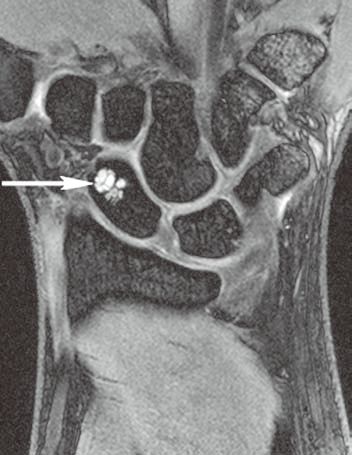

图1左腕手舟骨骨内腱鞘囊肿

A

B

C

D

左腕正位X线平片(A)示手舟骨远部骨内一小的透亮区。冠状位T1WI(B)示骨内病变呈低信号(箭)。冠状位(C)和横轴位(D)脂肪抑制T2WI示病变呈高信号,提示为液体(箭)